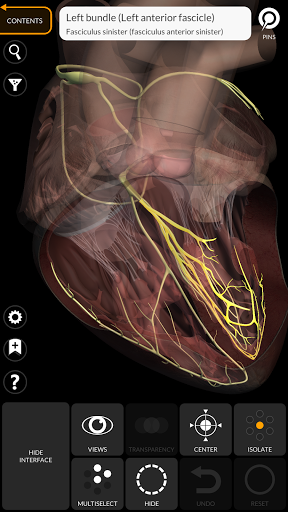

"Anatomy 3D Atlas" memungkinkan Anda mempelajari anatomi manusia dengan cara yang mudah dan interaktif.

Melalui antarmuka yang sederhana dan intuitif, Anda dapat mengamati setiap struktur anatomi dari sudut mana pun.

Model 3D anatomi sangat terperinci dan memiliki tekstur hingga resolusi 4k.

• Sistem kardiovaskular • Sistem

• Sistem kardiovaskular